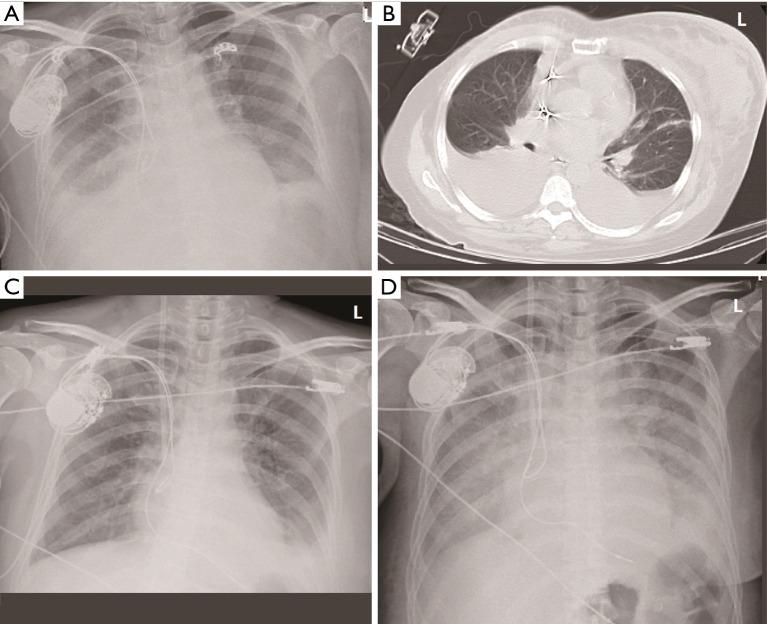

CASE DESCRIPTION

We describe a 45-year-old female who developed metastatic SBC 18 years after curative HL treatment. The diagnosis of TMA was established on the basis of thrombocytopenia, hemolytic anemia (elevated lactate dehydrogenase, low haptoglobin, and a reticulocyte count of 5.72%), and multi-organ dysfunction, following the exclusion of thrombotic thrombocytopenic purpura and Shiga toxin-producing (STEC)-hemolytic uremic syndrome. In this case, the multifactorial etiology-stemming from both paraneoplastic endothelial injury and chemotherapy-induced toxicity-complicated the clinical picture. Despite aggressive supportive measures, including plasma exchange and antibiotics, the patient's condition rapidly deteriorated, culminating in fatal cerebral hemorrhage.

我们描述了一名45岁女性,在接受HL根治性治疗18年后发生转移性SBC。在排除血栓性血小板减少性紫癜和产志贺毒素(STEC)溶血性尿毒症综合征后,根据血小板减少、溶血性贫血(乳酸脱氢酶升高、触珠蛋白降低以及网织红细胞计数为5.72%)和多器官功能障碍确诊为TMA。在该病例中,源于副肿瘤性内皮损伤和化疗诱导毒性的多因素病因使临床情况复杂化。尽管采取了积极的支持措施,包括血浆置换和使用抗生素,但患者病情迅速恶化,最终死于脑出血。